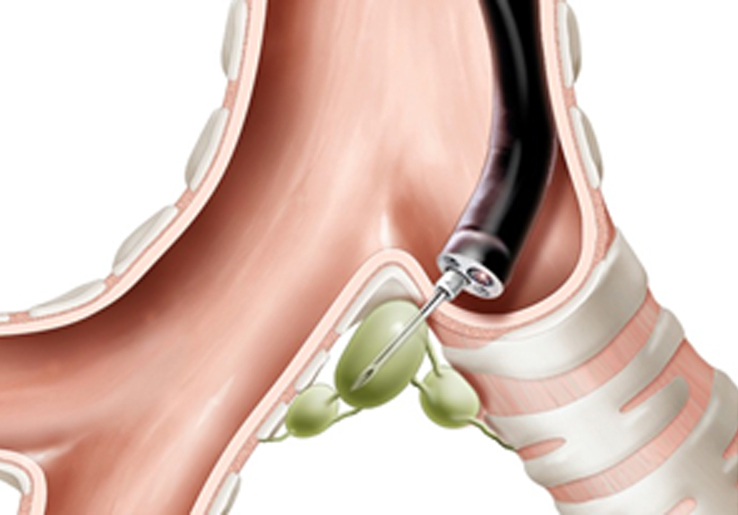

A bronchoscope is fitted with an ultrasound transducer at its tip. It is passed through your mouth, and down into your windpipe.

The transducer can be pointed in different directions to look at lymph nodes and other structures in the mediastinum (the area between your lungs).If the doctor sees any suspicious areas, such as enlarged lymph nodes, the doctor can take a sample of these areas using a needle passed through the bronchoscope.

Bronchoscope obtaining lymph node biopsy

Ultrasound guides lymph node biopsy

The samples are then sent to our pathologist to look at under the microscope.